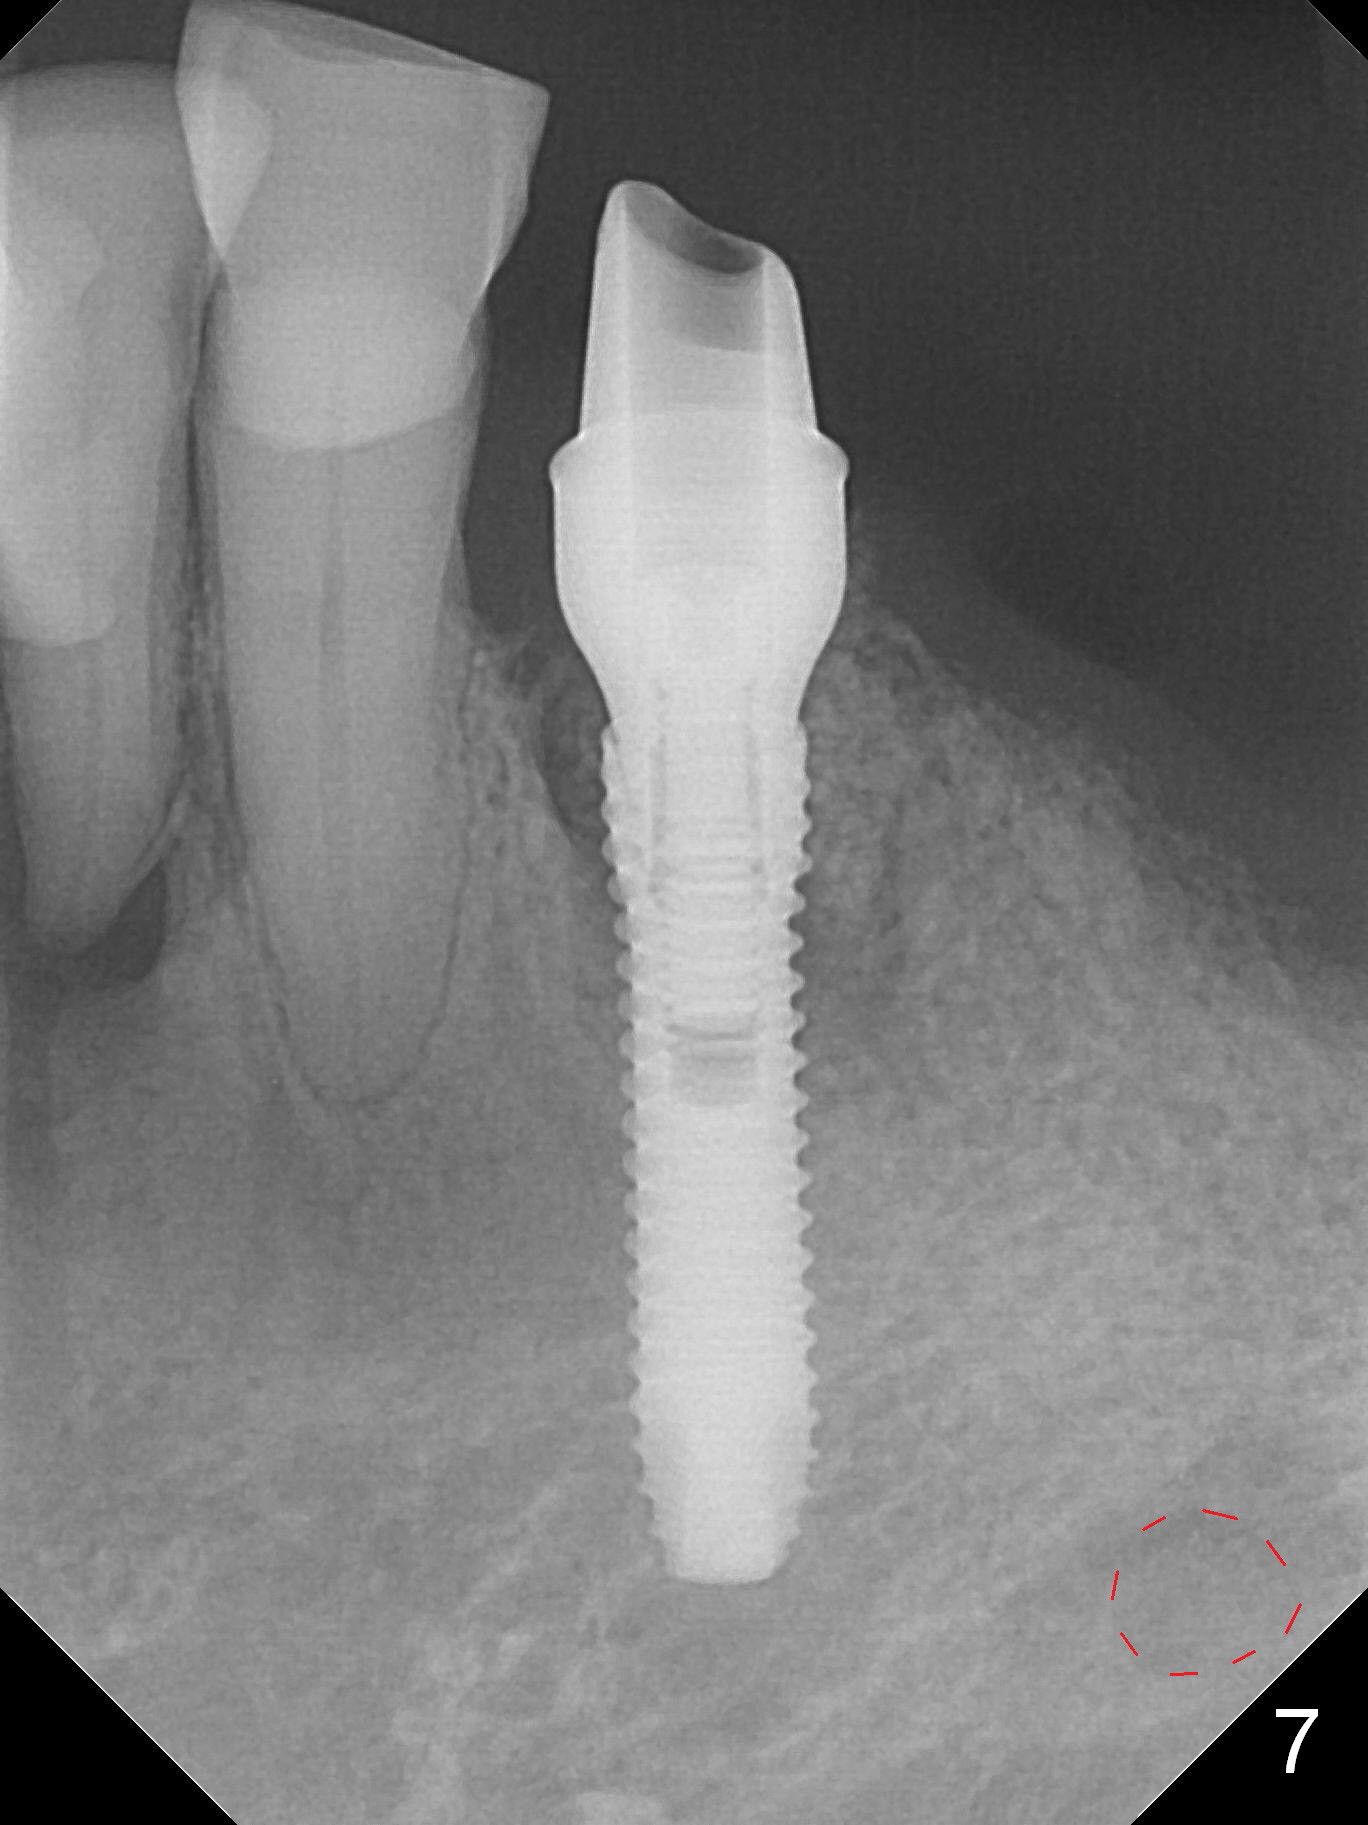

A 72-year-old man presents to clinic for implants because of pain associated with wearing the lower partial. The teeth #21, 24, 25 and 31 seem to be non-salvageable and are going to be replaced by implants so that the lower RPD can be reused (Fig.1). The edentulous ridge is atrophic (Fig.9 *). The upper complete denture appears to be functional. Since the tooth #21 is symptomatic (Fig.2) and the patient has chronic TMJ dislocation, the affected tooth is extracted first (Without antibiotic socket treatment) for immediate implant (Fig.3 (1.5 mm drill (placed more lingually)). The lower RPD is used as a surgical guide (Fig.4 (3 mm drill in place)). When a 3.8x16 mm implant is placed with bone graft (Fig.5 *), the underlying neurovascular bundle is undetected. A small field of panoramic X-ray is retaken; it seems that there is enough clearance from the Mental Foramen (Fig.2,6,7 (red dashed line)) and the Incisive Canal (pink dashed line). The implant is then placed 2 mm more apically (Fig.7) to reduce the chance of periimplantitis since the buccal plate is lost. A 5.5x5(5) mm abutment is placed (Fig.5) with more graft. The access of the abutment is left open so that a part of periodontal dressing is inserted for additional retention (Fig.8,9). The RPD is placed back for adaptation of the dressing. The patient is advised not to wear the RPD postop to reduce micromovement.